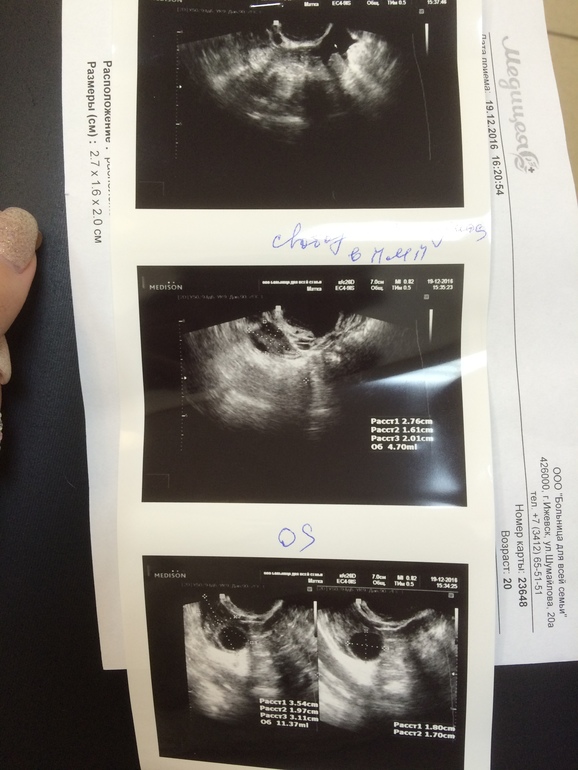

Ну что ,вчера в моем посте комментарии отнюдь не положительные были ))Ещё раз прилагаю тесты по сегодняшний день)Сходила я на узи,овуляция была !!!)и подозреваю что положительный тест был на 17 дц хоть и не яркий ,но на 17 дц из старой пачки была жирная полоска по ширине ))через день были выделения как сопли прозрачные .Эндометрий конечно 6,5 мм.Но я успела заскочить к гинекологу и она сказала что все возможно ,так что маленькая надежда у меня ещё есть

В том то и дело что вроде каждый день их делала с 9 дц)эвик пустой сегодня утром,только до меня не доходит анэхогенное образование это кистозное состояние желтого тела?

Почему кистозное, нормальное жт у тебя, просто не все узисты пишут жт, некоторые анэхогенное образование.

Получается овуляция была в правом яичнике?а то просто после гинеколога ехала и думаю а где в узи написано про жт🤔на 16 дц на узи жидкости не было,а сейчас есть т.е это точно овуляция была,вот чёт я забеспокоилась про жт

Да, в правом яичнике. Анэхогенное образование - это жт. А жидкость означает,что О была недавно) ждем тест на Б с //)

Как говорится надежда умирает последней))эндик только смущает)но гиня сказала у ее пациентки и на 4 мм зачатие произошло )только теперь опять запуталась )на 16 дц доминантный в левом 16 мм ,а в правом 14 мм и как так что в правом случилось ?

Узистка сказала киста у меня справа и не понимала почему жидкость,короче если бы не моя гиня я бы проревела весь вечер

Она жт за кисту приняла просто. Бывают такие экземпляры. Нормальные узисты когда сомневаются жт, дф или киста, включают режим цдк или доплер и смотрят кровоток.